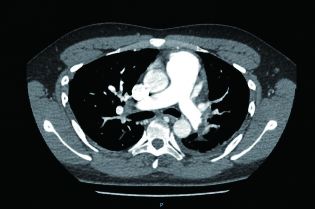

例4 62岁,女性,主诉“活动后气短20 d,加重1 d伴晕厥1次”。患者入院20 d前上近20级台阶后感气促,休息后缓解,未重视。入院前1 d,突发晕厥伴有轻微活动后明显的呼吸困难。既往:左下肢静脉曲张病史3~4年;入院40 d前患者左足跖骨骨折,接受外固定,尚未影响日常活动,未接受抗凝治疗;发现血小板减少数年(血小板维持5.5~8.6 g/L,末次于一年前血小板85 G/L),未明确原因及治疗;血气分析提示pH 7.447,PaCO2 32.2 mmHg,PaO2 85.3 mmHg,SaO2 96.8%;D-Dimer 1 947 ng/mL;FDP 22.84 μg/mL,FBG 2.05 g/L;PLT 51G/L;cTnI 0.52 ng/mL,BNP 299 pg/mL;ALT 318 U/L,AST 300 U/L,CREA 74.8 μmol/L,血Na+、K+、Cl-:正常范围;UCG提示:右心大,肺动脉主干轻度增宽(28 mm),三尖瓣反流(重度),反流面积13.7 cm2,TI法估计SPAP为30 mmHg、左室舒末内径35 mm、左室舒张功能受限(E/A 1:1.5)、未见节段性室壁运动障碍;双下肢静脉超声提示左侧腘静脉不完全血栓。心电图(图 12所示)提示窦性心动过速、SⅠQⅢTⅢ;CTPA显示肺动脉分叉处及双肺亚段充盈缺损(图 13所示)。

| 图 13 入院时CTPA结果显示肺动脉分叉处及双肺亚段充盈缺损 |

入院查体:神志清楚,体温36.5℃,血压120/70 mmHg,脉率110次/min,呼吸22~26次/min,指氧饱和度93%(安静,空气氧),未见乏氧征。双肺呼吸音清,未闻及干湿性啰音,心率110次/min,律齐,P2 > A2,心界无扩大,无杂音,腹软,无压痛,肠鸣音正常。神经系统未见异常。左下肢膝关节以下可见静脉曲张,双下肢无浮肿。入院诊断:急性肺血栓栓塞症(中高危);左下肢静脉曲张并血栓形成;血小板减少症;肝功能不全。处理方法及原因:患者中年,日常生活质量高;入院20 d前虽有症状,但入院1 d前明显加重并出现晕厥发作;两次D-Dimer检查均<2 000 ng/mL,与CTPA显示的血栓负荷不匹配。入院后连续两次检测血小板均低于正常(51~77 g/L)。因考虑病史较长但近期有加重、血小板低等原因系统溶栓治疗出血风险较大,所以给予导管介入碎栓并行肺动脉内溶栓治疗(r-tPA 20 mg)。溶栓2 h后患者症状明显缓解,复查D-Dimer 12 560 ng/mL,序贯肝素抗凝并复查CTPA提示原有血栓明显消失(图 14所示)。

| 图 14 介入溶栓后患者CTPA结果提示明显改善 |

患者特点及再灌注治疗时机及方式选择:患者病程20 d,但是入院前1 d呼吸困难加重同时伴有晕厥,提示1 d内有明确的新的血栓脱落导致的一过性脑缺血。理论上讲,如果纤溶功能正常的话,CTPA显示的血栓负荷与D-Dimer具有一定的匹配性,而本例患者连续两次检测并未发现这种匹配的特点,分析原因有两种可能:①原有主肺动脉干血栓负荷较大,近期虽然有新的血栓脱落,但新鲜血栓的负荷量不足以大到D-Dimer明显升高的地步;②主干血栓为近期一次脱落而成,但是患者有存在继发纤溶低下的可能,同样表现为较低的D-Dimer水平。如果存在继发纤溶功能低下的话,难以避免单纯抗凝治疗后栓塞性肺动脉高压的风险。我们决定给予介入下的碎栓并肺动脉内溶栓治疗是考虑原有血栓阻塞左右肺动脉主干,很难代偿新鲜血栓的再次脱落。更重要的是,CTPA提示肺动脉主干的骑跨血栓密度尚不支持陈旧血栓。溶栓后CTPA结果也验证了对CTPA结果解读的正确。本例患者另一个特点D-Dimer水平与血栓负荷不成比例的另一个依据是凝血机制检测提示纤溶系统异常,PAI-1活性超过正常3倍,证实了最初的判断。